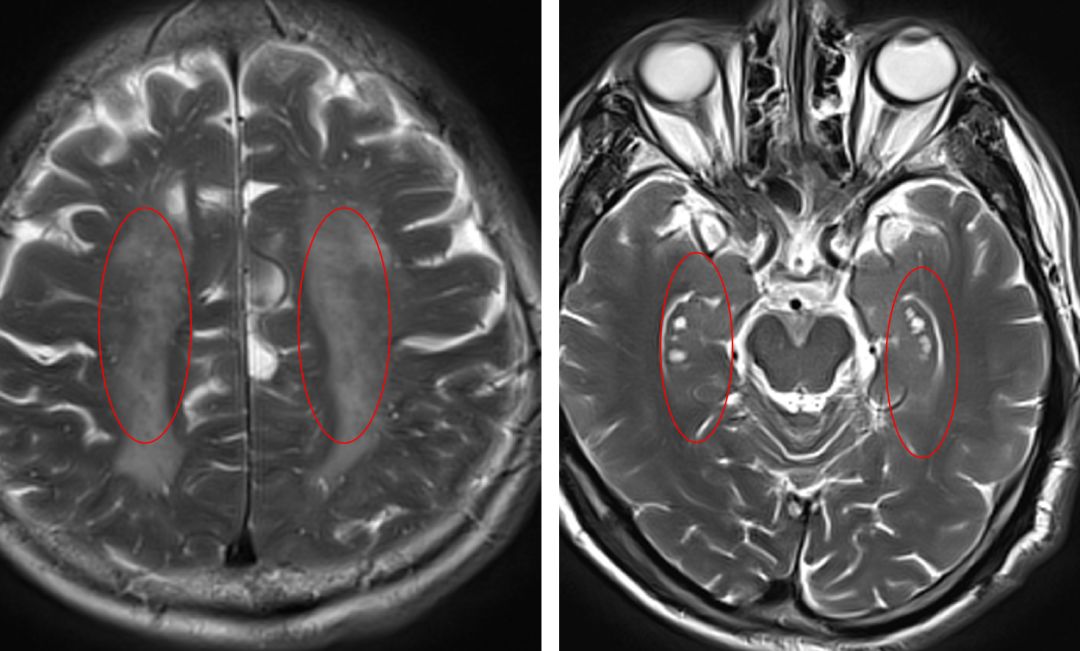

脑白质病变(左)血管周围间隙(右)

腔隙性脑梗死

脑微出血